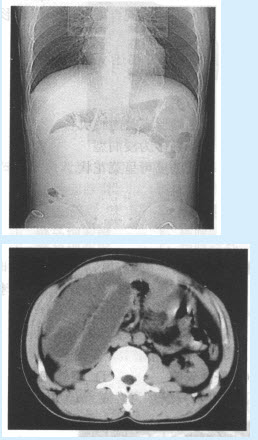

患者,男,35岁。急性腹痛,呕吐,腹胀,面色苍白入院,行平片及CT检查,如图。

结合病史应该诊断为()

A:麻痹性肠梗阻

B:单纯性肠梗阻

C:绞窄性肠梗阻

D:痉挛性肠梗阻

E:乙状结肠扭转

F:肠套叠